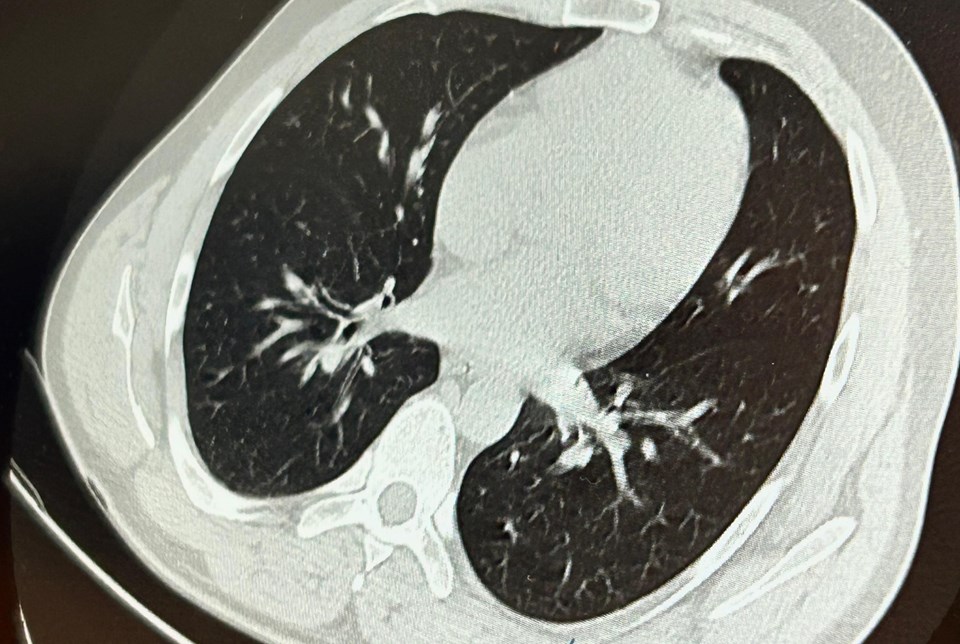

Hastaya bronkoskopi işlemi uygulandı. Sol akciğerin üst lobunda saplanmış şekilde tespit edilen vida, vidalı yapısı ve bulunduğu konum nedeniyle güçlükle yerinden oynatılabildi.